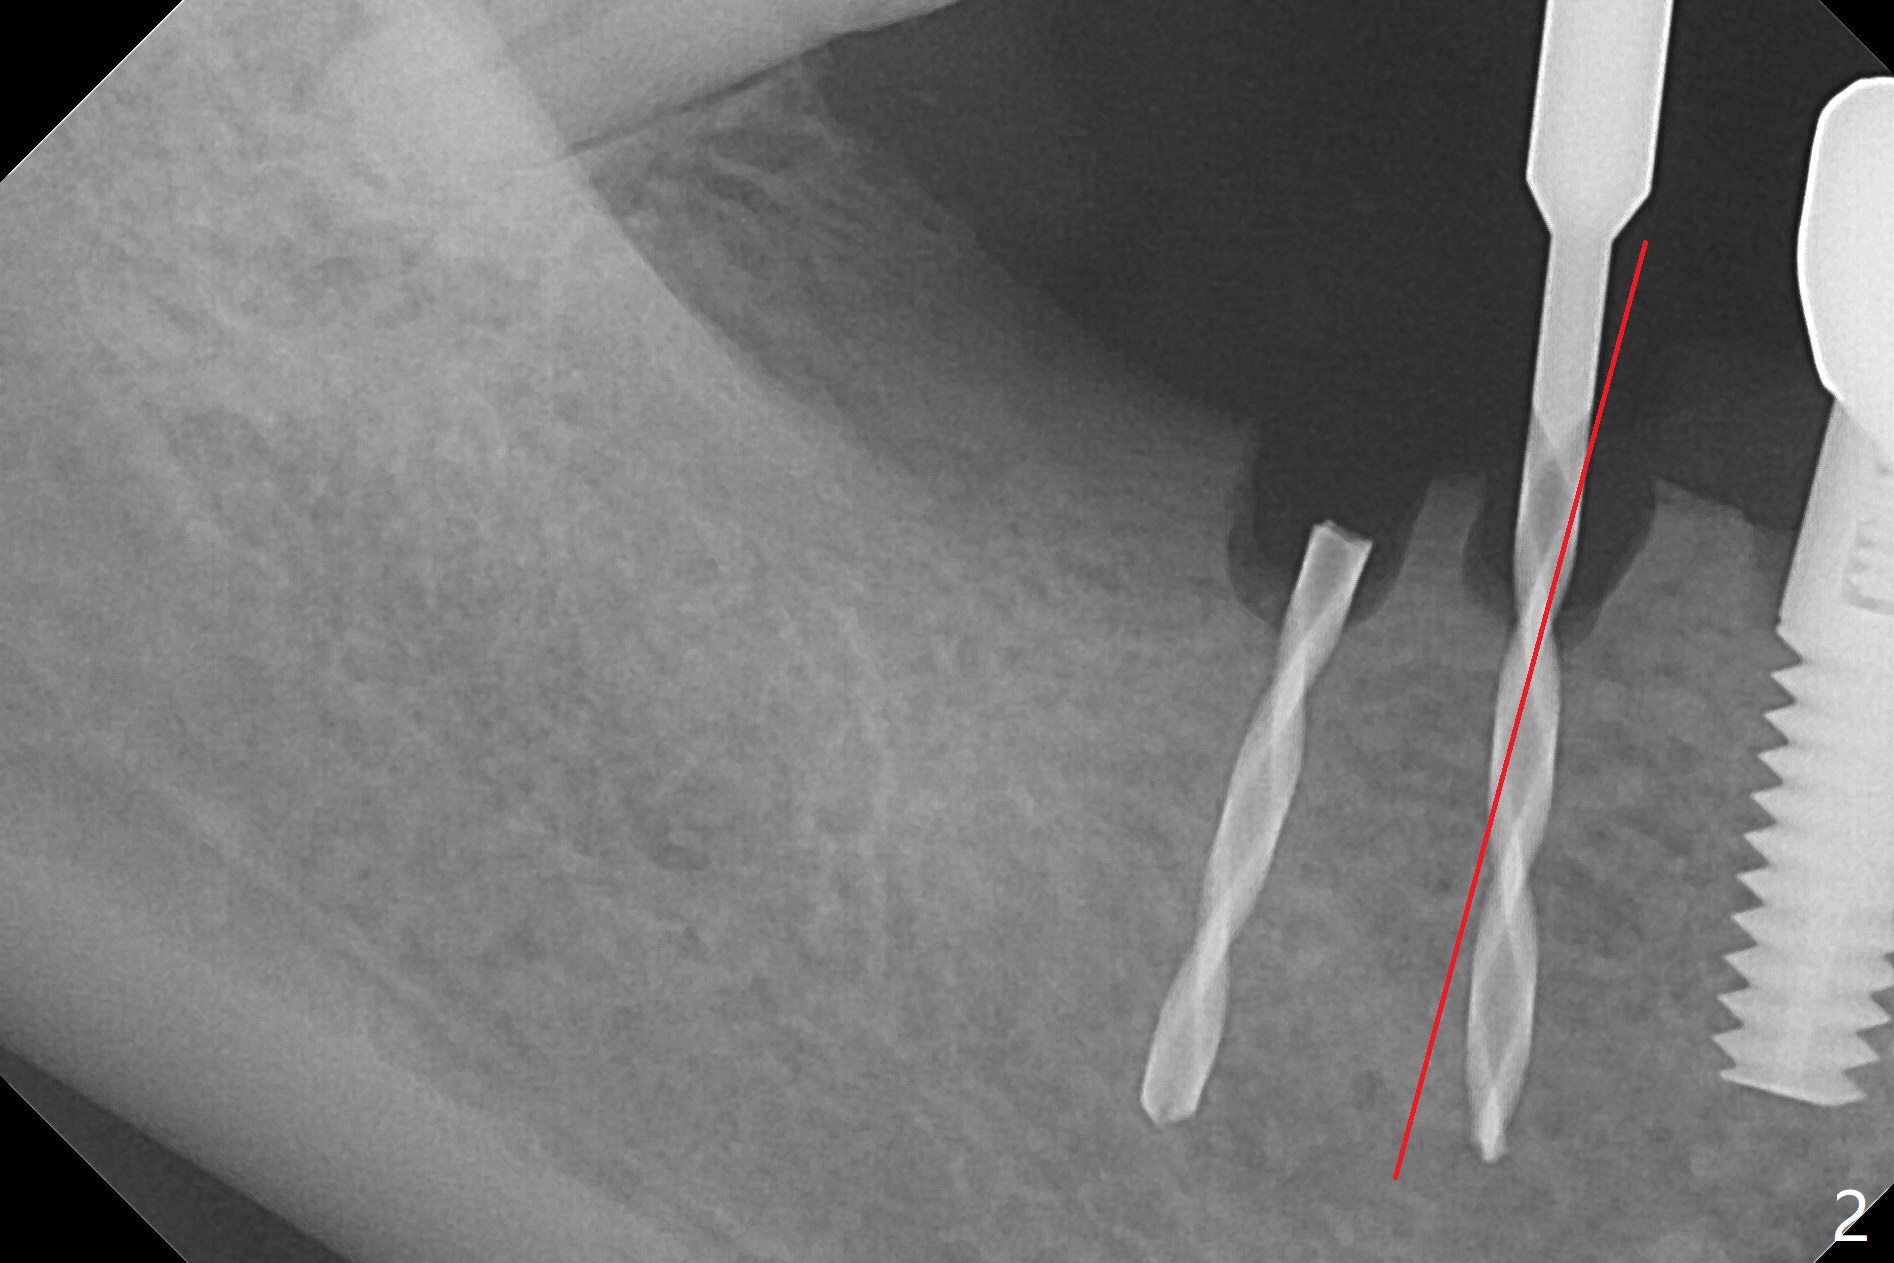

Two of 2.5 mm 1-Piece Implants M

The edentulous ridge at #30 is narrow (Fig.1). After ridge reduction, osteotomy is initiated with 1.2 mm drill for 10 mm; the mesial osteotomy is to be changed (Fig.2 red line). Using a 1.2 mm drill placed in the distal osteotomy (Fig.3 D), the mesial osteotomy changes in trajectory with subsequent placement of a 2.5x10(4) mm 1-piece implant. Since the mesial implant is high in occlusion, the cuff of the distal implant is changed to be 2 mm (Fig.4 (shorter black line)). Panoramic X-ray is taken to show no violation of the Inferior Alveolar Canal (Fig.5 red dashed line). These two 1-piece implants are slightly lingually placed (Fig.6). The crestal bone around the implants resorbs without thread exposure 5 months postop (Fig.7). Impression is taken for a splinted crown (Fig.8-12). There is no metal show around the 2.5 mm 1-piece implants 6 months postop (advantage) vs. that at #28 and 29 (Fig.13). Bitewing is taken post cementation to determine whether residual cement is present (Fig.14). There is periodic swelling and pain in the lower right quadrant 2 years post cementation (Fig.15). In fact periimplantitis appears to have developed at #28 (Fig.16) with loss of the buccal bone (Fig.17,18). The buccal bone loss is less at #29 (Fig.19) and #20 (Fig.23) and no at #30 mesial and distal implants (Fig.20,21). A much smaller implant will be placed lingually at #28 immediate (Fig.24,25).